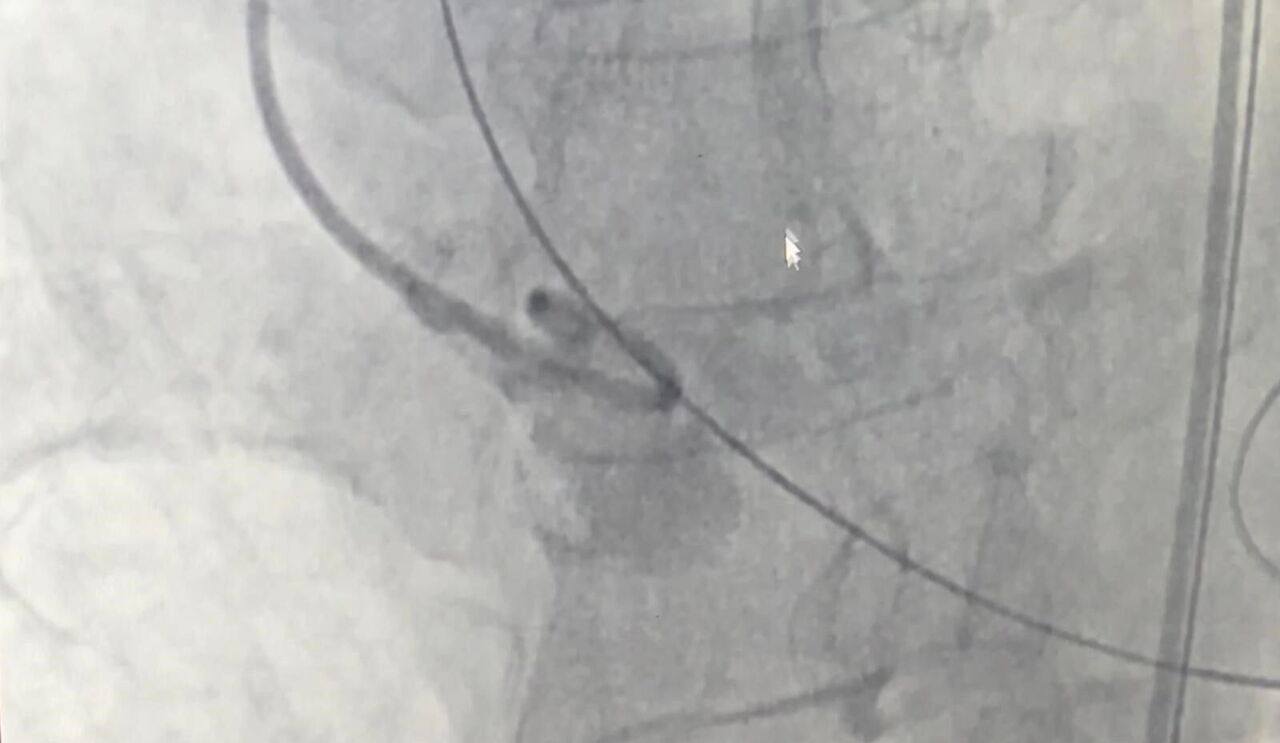

Doç. Dr. Yenerçağ, işlem öncesi yapılan tetkiklerde karşılaştıkları nadir bulgu hakkında ise "Hastanın TAVİ işleminden önce yapılan tetkiklerinde aort kapağının 3 yaprakçıklı olması beklenirken çok daha nadir görülen ‘Quadricuspid’ adı verilen 4 yaprakçıklı aort kapağı saptadık. Daha önce böyle bir vaka ile karşılaşmamıştık. Literatürleri, akademik çalışmaları inceledik. 4 yaprakçıklı aort kapağının toplumda 100 bin kişide 4 görüldüğünü, taradığımız uluslararası yayınlarda ise 4 yaprakçıklı aort kapağı bulunan sadece 17 hastaya TAVİ işlemi yapıldığını saptadık. Ülkemizden bildirilen vaka örneği bulamadık. Diğer ülkelerde yapılan vakaları detaylıca inceledik. İleri tomografik analizleri yaptık. Vakamıza detaylıca hazırlandık" dedi.

"Doç. Dr. Serkan Sivri, asistan doktorlarımız Berkan Öztürk ve Enes Kaya ile Anestezi Uzmanı Aynur Kaynar hocamızla beraber ekip halinde hastamıza başarılı TAVİ işlemini yaklaşık 50 dakika içerisinde tamamladık. Hastamızı 1 gün yoğun bakımda takip ettikten sonra servis takibine aldık. Nadir görülen bu 4 yaprakçıklı aort kapağına yaptığımız TAVİ işleminin prosedürel detaylarını literatüre kazandırmayı planlıyoruz. Bizden sonra bu nadir vaka ile karşılaşan meslektaşlarımıza yol göstermesi açısından referans olacaktır."